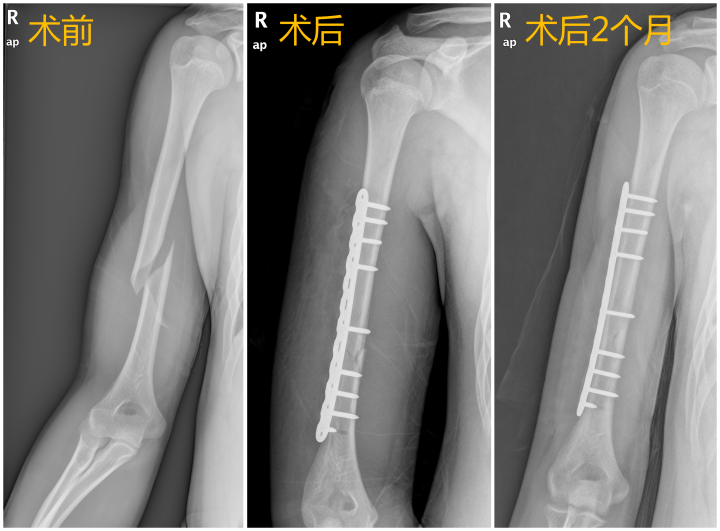

“从X片看,患者的右侧肱骨中下段有明显的螺旋形骨折。”由于骨折移位产生剧烈痛感,手法复位后梁博程先帮小源右上臂打上石膏进行临时固定,以限制骨折处的活动,缓解疼痛,以及预防二次损伤导致的右侧桡神经损伤。

“对于肱骨干没有移位或者位置较好,能保持稳定的,一般可采取保守治疗。”梁博程解释道,但小源第二日的复查结果并不理想,拍CT显示骨折移位明显,石膏固定也不能维持良好对位,需要进一步手术治疗。

经与小源及家属充分沟通,完善术前评估后,骨伤二科团队为小源做了右肱骨骨折切开复位内固定手术。术后配合中药辨证内服和远红外理疗,以及康复医生指导下积极进行康复训练,小源恢复得很快,定期复查骨折愈合情况良好,2个月后骨折已基本愈合,目前右手臂已逐渐恢复原来的功能。